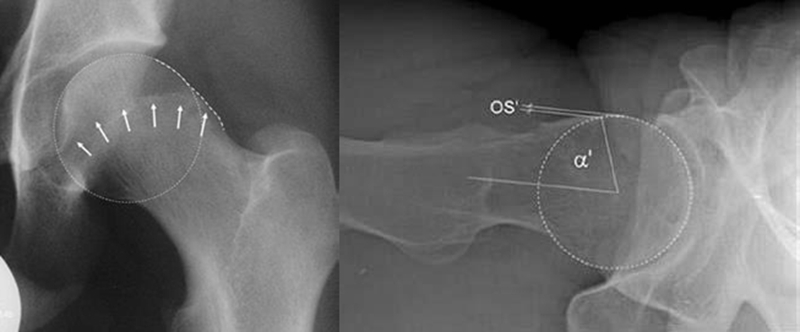

对于髋关节撞击综合征的诊断,不同于髋关节骨性关节炎或者股骨头坏死的患者,不能仅仅通过普通的X光片和双髋关节核磁共振就能确诊,因为造成髋关节撞击综合征的异常骨性凸起通常位于髋臼或者股骨头颈结合区的前外侧,所以临床上常规的髋关节正侧位片上,这个骨性异常的区域恰恰被遮挡了起来,在X光片上成了重叠的影像。在诊断髋关节撞击综合征,会采用一些特殊的影像拍摄方法。对于X光的选择,推荐进行骨盆正位相联合蛙式侧位或Dunn位像。对于盂唇损伤的诊断主要依赖于核磁共振检查,由于双髋关节核磁共振放大率以及扫描方向的问题,不足以判断盂唇的状态,一般需要进行单髋关节核磁共振扫描。

图6 摘自Tannast M, Siebenrock KA, Anderson SE. Femoroacetabular impingement: radiographic diagnosis-what the radiologist should know[J]. Am J Roentgenol, 2007,188(6):1540-1552